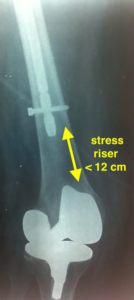

- Απόσταση μεταξύ εμφυτευμάτων μικρότερη των 12 εκατοστών αποτελεί προδιαθεσικό παράγοντα για περιπροθετικό κάταγμα.

- Τεχνικά (ιατρικά) λάθη. Δυστυχώς είναι ένα μεγάλο πρόβλημα που σχετίζεται φυσικά με την εμπειρία του χειρουργού, ο τρόπος εμφύτευσης μίας πρόθεσης ή ο λανθασμένος τρόπος της οστεοσύνθεσης, τελικά προδιαθέτει σε δημιουργία περιοχών με αυξημένες συγκεντρώσεις φορτίων (sress risers) που με τη σειρά τους προδιαθέτουν σε περιπροθετικό κάταγμα.

- Σε περίπτωση τοπικής οστικής απώλειας, μπορεί να τοποθετηθεί ειδικό μόσχευμα (π.χ φλοιώδες οστούν), ώστε να ενισχύσει την οστεοσύνθεση ή να τοποθετηθεί επιπλέον πλάκα ώστε να εξαφανίσει τις συγκεντρώσεις φορτίων (stress risers)